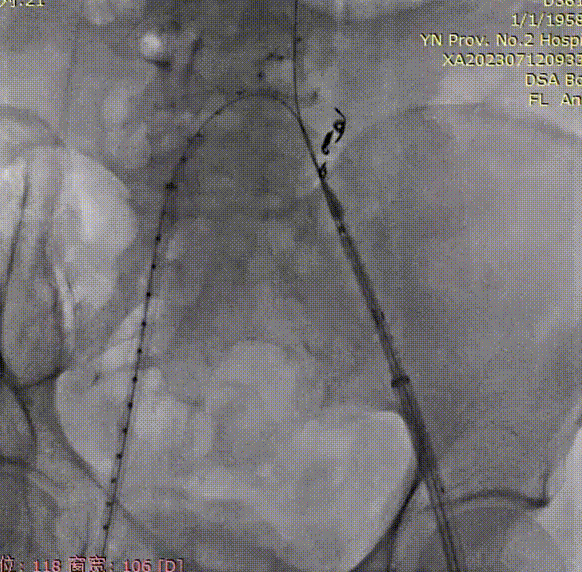

导管内手推造影,确认右髂内超选成功;

gore医疗怎么样「漫腹精论」双股动脉入路,纯腔内保双髂——GORE® EXCLUDER® 髂动脉分支型覆膜支架(IBE)治疗双侧髂总动脉_https://www.jmylbn.com_新闻资讯_第23张

右髂内支架通过IBE短腿后,整体往下拉IBE,将IBE短腿拉至右髂内动脉开口上方;